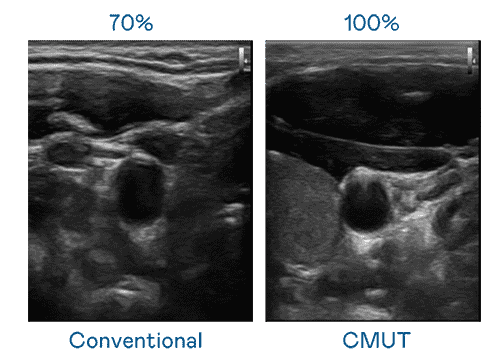

CMUT 技术是一种用电容式微机电元件来产生超音波讯号的技术。。。。与传统 PZT 压电式技术相比,,,CMUT 频宽增加 30%,,更宽频的超音波讯号让影像解析度大幅提升,,是实现高影像品质医疗超音波扫描、、促进精准医疗发展的关键技术。。。

大频宽带来超清晰影像

超音波影像的解析度高低,,,,首先取决于探头能发出的讯号频宽。。。MG电玩 CMUT 可提供高清晰的超音波讯号,,,提供高频宽、、高灵敏度、、、影像纹理细节更高的超音波影像,,协助医护人员缩短影像判读时间及利用精准的医疗影像进行诊断。。。